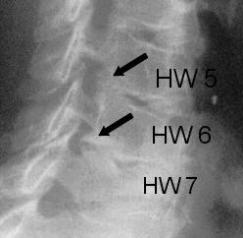

Die Myelograhie dient der speziellen Darstellung des Wirbelkanals im Röntgen-Bild. Dazu wird zunächst durch Lumbalpunktion ein wasserlösliches Kontrastmittel in den Wirbelkanal eingebracht. Die Untersuchung wird bei besonderen Fragestellungen betreffs raumfordernder Prozesse des Spinalkanals, oder bei der Diagnostik ausgeprägter degenerativer Veränderungen im Bereich von Hals- oder Lendenwirbelsäule eingesetzt.